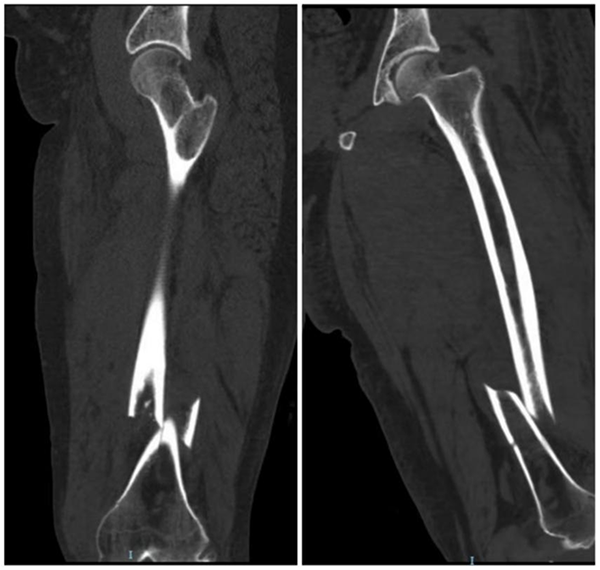

图中所示为患者的术前影像

入院后,医护人员第一时间完善各项相关检查,明确诊断为左股骨干骨折、膝关节血友病性关节病,且其为既往血友病A型患者。据介绍,血友病是一种X染色体连锁的隐性遗传性出血性疾病,因凝血因子Ⅷ或Ⅸ基因缺陷,导致患者终身凝血功能异常;其中血友病A占比达80%~85%,患者以男性为主,核心临床表现为自发性出血或轻微损伤后出血不止,反复出血还可能引发关节病变、肢体残疾等严重并发症。而李先生此次所患的股骨干骨折,属于高能量损伤导致的不稳定骨折,保守治疗无法维持下肢骨骼的对位对线,虽具备明确的手术指征,但血友病带来的凝血功能障碍,让这场手术成为临床诊疗中名副其实的“禁区手术”。